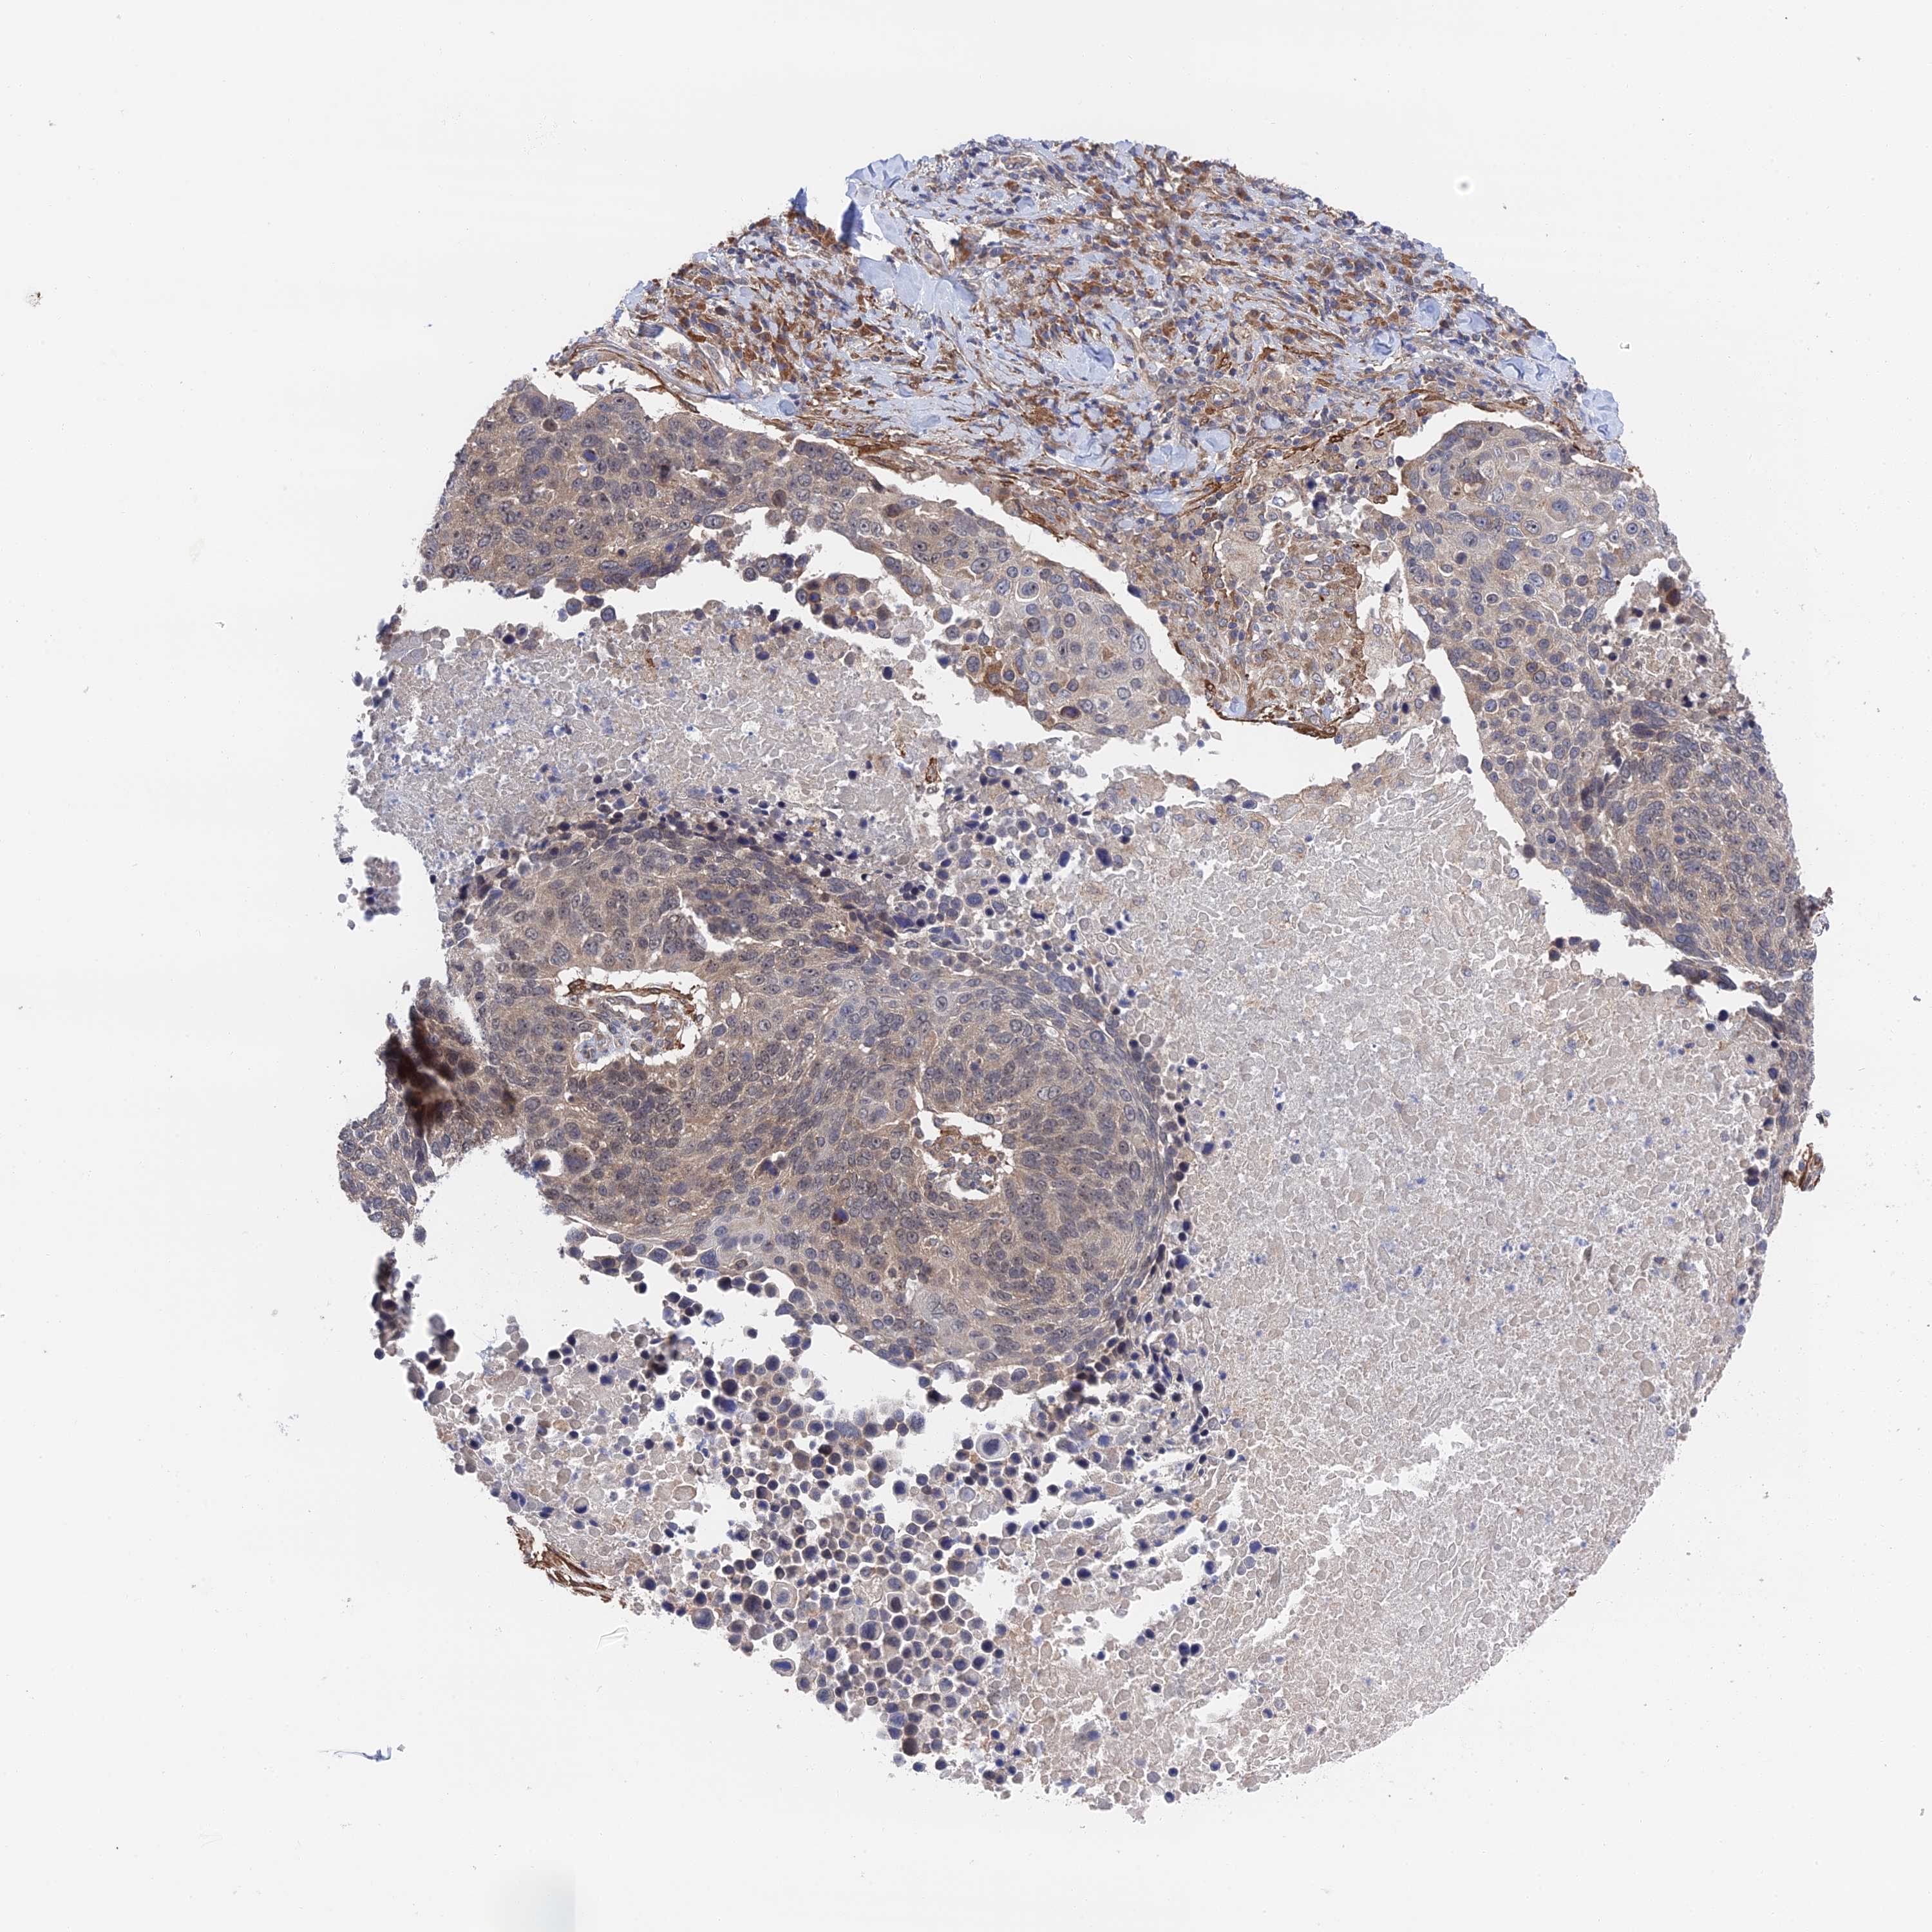

LUNG SQUAMOUS CELL CARCINOMA (TCGA) - Interactive survival scatter ploti

The Survival Scatter plot shows the clinical status (i.e. dead or alive) for all individuals in the patient cohort, based on the same data that underlies the corresponding Kaplan-Meier plots. Patients that are alive at last time for follow-up are shown in blue and patients who have died during the study are shown in red.

The x-axis shows the expression levels (FPKM) of the investigated gene in the tumor tissue at the time of diagnosis. The y-axis shows the follow-up time after diagnosis (years). Both axes are complimented with kernel density curves demonstrating the data density over the axes. The top density plot shows the expression levels (FPKM) distribution among dead (red) and alive patients (blue). The right density plot shows the data density of the survived years of dead patients with high and low expression levels respectively, stratified using the cutoff indicated by the vertical dashed line through the Survival Scatter plot. This cutoff is automatically defined based on the FPKM cutoff that minimizes the p-score. The cutoff can be changed by dragging the vertical line or by entering a cutoff value in the square labeled "Current cut-off".

Under the Survival Scatter plot the p-score landscape (black curve; left axis) is shown together with dead median separation (red curve; right axis). Dead median separation is the difference in median mRNA expression between patients who have died with high and low expression, respectively. It is calculated as follows: median FPKM expression of dead patients with high expression - median FPKM expression of dead patients with low expression. This is intended to aid the user in visually exploring custom cutoffs and the associated p-scores and dead median separation.

Individual patient data is displayed and can be filtered by clicking on one or more of the category buttons on the top of the page. Categories describing expression level and patient information include: high, low, alive, dead, female, male and tumor stages. The scale of the x-axis can be toggled between linear and log-scale by clicking on the "x log" button. Mouse-over function shows TCGA ID, patient information and mRNA expression (FPKM) for each patient.

& Survival analysisi

Kaplan-Meier plots summarize results from analysis of correlation between mRNA expression level and patient survival. Patients were divided based on level of expression into one of the two groups "low" (under cut off) or "high" (over cut off). X-axis shows time for survival (years) and y-axis shows the probability of survival, where 1.0 corresponds to 100 percent.

ZNF320 is not prognostic in Lung Squamous Cell Carcinoma (TCGA)

: 4.06

P scorei

N/A

Average pTPM 7.2

Number of samples 489